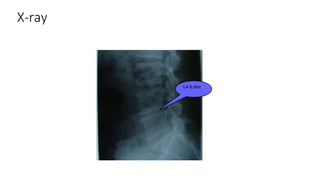

X-ray

• #46 Evaluation Over 85 to 90% of patients with an acute herniated disc experience relief of symptoms within 6 to 12 weeks without any treatments. Patients without radiculopathy notice an improvement in even less time. Due to the high prevalence of disc herniation in routine neuroimaging of asymptomatic individuals, the recommendation is to avoid ordering imaging studies during this period as the study results will not alter the management. However, further evaluation and imaging are warranted if there is a clinical suspicion of severe underlying pathology or neurological compromise. Imaging and laboratory tests are indicated in patients who exhibit red flag symptoms. In patients who are unresponsive to conservative treatment after two to three months, imaging is also recommended. Laboratory tests: Erythrocyte sedimentation rate and C-reactive protein are inflammatory markers, and they are requested if suspicious for a chronic inflammatory condition or infectious cause as the etiology. A complete blood count is useful when suspecting infection or malignancy. X-rays: Lumbar X-ray films are the first-line imaging test performed in low back pain settings. The standard examination includes three views (AP, lateral, and oblique) to evaluate the overall alignment of the spine, detecting fractures, as well as degenerative or spondylotic changes. Lateral flexion and extension views are useful in assessing spinal instability. Narrowed intervertebral space, traction osteophytes, and compensatory scoliosis on X-ray are findings that usually suggest lumbar disc herniation. If an acute fracture is detected, further investigation with computed tomographic (CT) scan or magnetic resonance imaging (MRI) is required. CT: This is the most sensitive imaging modality to examine the bony structures of the spine. CT imaging allows for the evaluation of calcified herniated discs or any pathological process that may result in bone loss or destruction. It is deficient for the visualization of nerve roots, making it unsuitable in the diagnoses of radiculopathy. CT myelography is the imaging modality of choice to visualize herniated discs in patients with contraindications for an MRI. However, due to its invasiveness, the assistance of a trained radiologist is required. Myelography is associated with risks like post-spinal headache, meningeal infection, and radiation exposure. Recent advances with a multidetector CT scan have made the diagnostic level of it nearly equal to the MRI.[12] MRI: Is the gold standard study for confirming a suspected LDH. With a diagnostic accuracy of 97%, it is the most sensitive study to visualize a herniated disc due to its significant ability in soft tissue visualization. MRI also has higher inter-observer reliability than other imaging modalities. It suggests disc herniation when it shows an increased T2-weighted signal at the posterior 10% of the disc. Degenerative disc diseases have shown a correlation with Modic type 1 changes.[13] When evaluating for postoperative lumbar radiculopathies, the recommendation is that the MRI is performed with contrast unless otherwise contraindicated. MRI is more effective than CT in distinguishing inflammatory, malignant, or inflammatory etiologies of LDH. It is indicated relatively early in the course of evaluation (<8 weeks) when the patient presents with relative indications like significant pain, neurological motor deficits, and cauda equina syndrome. Diffusion tensor imaging is a type of MRI sequence used for detecting microstructural changes in the nerve root. It may be beneficial in understanding the changes that occur after herniated lumbar disc compresses a nerve root, and might help in differentiating the patients that need surgical intervention. In patients with a high suspicion of radiculopathy due to lumbar disc herniation, yet the MRI is equivocal or negative, nerve conduction studies are indicated.[1][5][8][9]